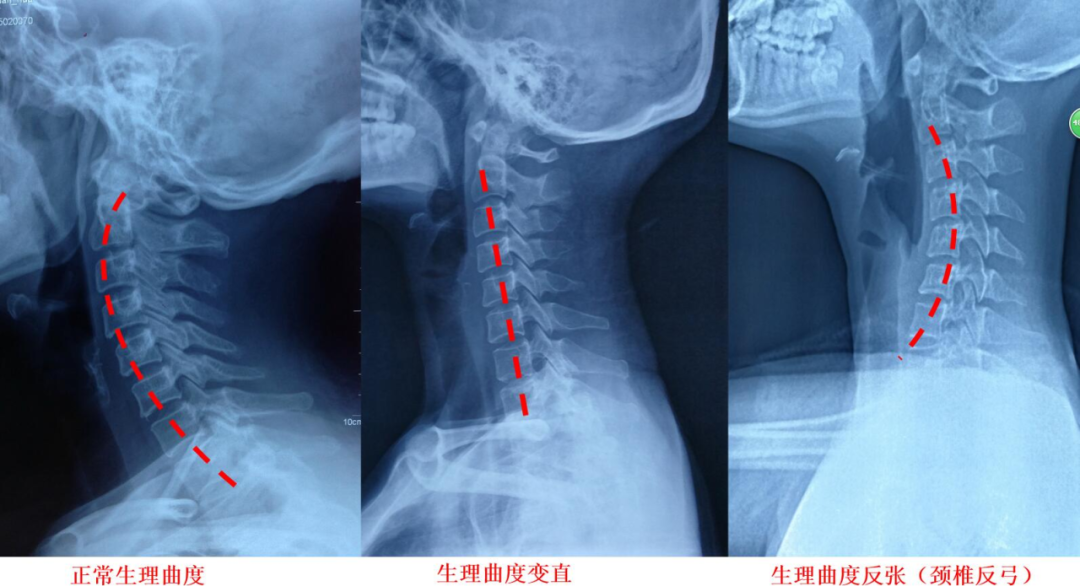

我们颈椎的正常生理弧度是呈一个“C”字型,要想睡得舒服,枕头就得贴合承托我们的脖颈这个“大C”。